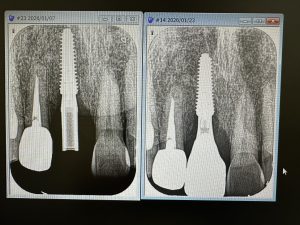

骨がモリモリ、ワイドインプラント径6.5ミリは非常に良い、安定性👌

大臼歯には幅、径ワイドが必須!

表面積を頭に入れ、choice‼️

噛み合わせ不調和、径小さい為に、本体破折、中ネジの緩みに破折やら色々トラブルが発生するから、トラブルにならないような知識がないとね〰︎💪